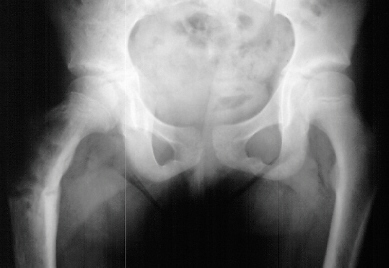

A 10 year old white female was evaluated in the orthopaedic clinic for leg length discrepancy. Her disease process has been characterized by early breast development at 3 years of age, menarche at the age of 6, and a pathologic subtrochanteric fracture after a trivial fall at age 8. She now complains of a limp and pain after long walks. The patient demonstrated a large pigmented lesion with irregular border located in the right upper back. There was a two centimeter leg length discrepancy by the block test.

Because this is a girl, she is much more likely to have multiple bones involved.